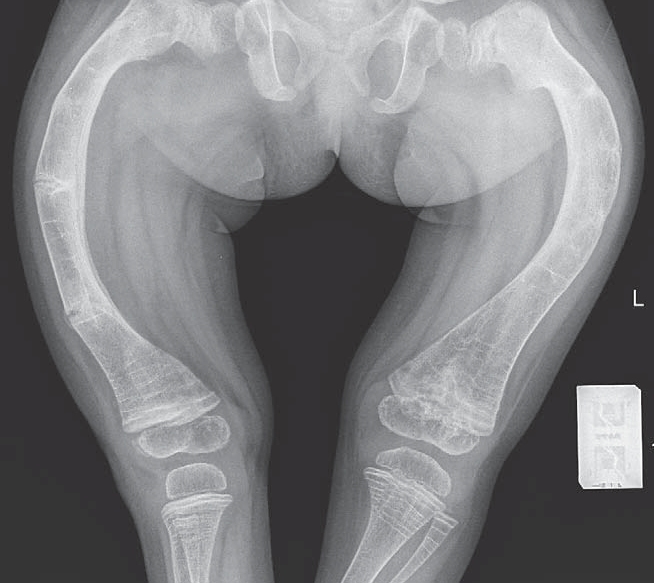

Type II osteogenesis imperfecta is het ernstigste type en veroorzaakt de dood. Zuigelingen worden meestal geboren met veel gebroken botten. De schedel kan zo zacht zijn dat de hersenen niet beschermd zijn tegen de druk die tijdens de bevalling op het hoofd wordt uitgeoefend. Deze zuigelingen hebben verkorte armen en benen en blauwe sclerae. Zuigelingen met dit type kunnen vóór de bevalling of binnen de eerste dagen of weken van hun leven overlijden.

Röntgenfoto's kunnen een abnormale botstructuur aantonen die wijst op osteogenesis imperfecta.